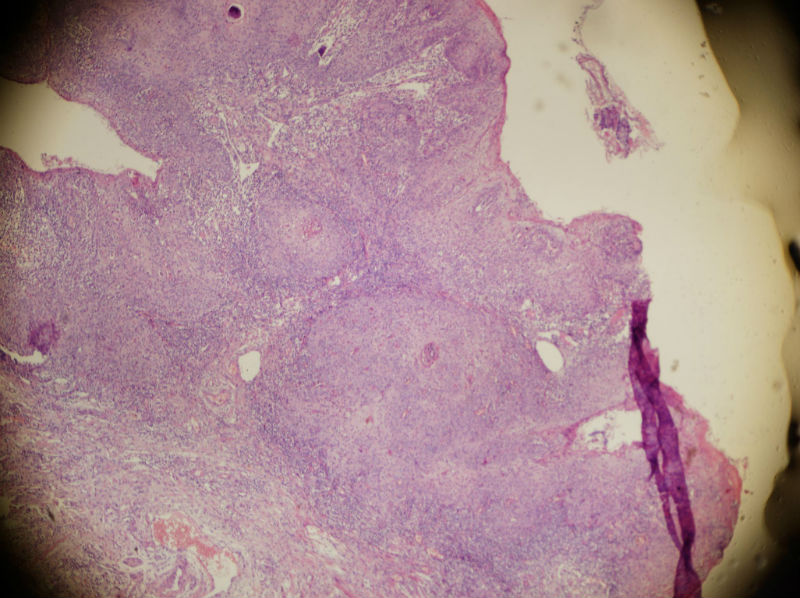

男,45岁,上唇菜花样肿物,请老师指教

图4